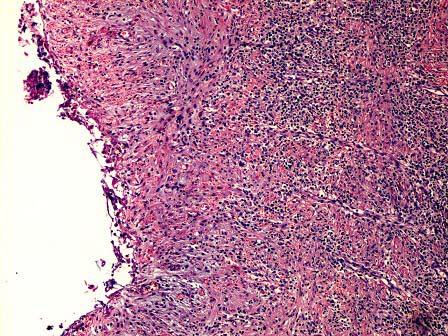

问题 某肾脏病理切片如图所示,镜下可见 ( )

选项 A.浆液性炎 B.纤维素性炎 C.化脓性炎 D.出血性炎 E.以上都不正确

答案 C